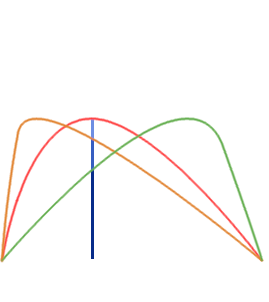

Multi Echo (ME-fMRI)

- Single Echo (SE): during fMRI acquisition we collect the signal once per TR at a certain TE to obtain one timeseries per voxel

-

Multi Echo (ME): we collect the signal multiple times at different TEs to obtain n timeseries per voxel

Multi Echo (ME-fMRI)

- Single Echo (SE): during fMRI acquisition we collect the signal once per TR at a certain TE to obtain one timeseries per voxel

-

Multi Echo (ME): we collect the signal multiple times at different TEs to obtain n timeseries per voxel

Optimal combination

For each voxel and TR, we can Optimally Combine the echo volumes with a weighted sum based on their contribution to \( T_2^{\star} \)

In this way, spatial CNR and tSNR are maximised and the signal can be recovered in areas of drop-out

Posse et al. 1999 (Magn Reson Med)

ME-ICA

Assuming monoexponential decay, we can express the

signal percentage change as:

\[ S_{SPC} \approx \Delta\rho - TE \cdot \Delta R_2^{\star} + n \quad where \enspace R_2^{\star} = \frac{1}{T_2^{\star}} \]

This let us differentiate BOLD-related (\(\Delta R_2^{\star}\)) from non-BOLD related (\(\Delta\rho\)) changes

Kundu et al. 2012 (NeuroImage)